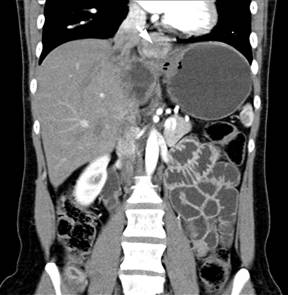

Based on this, 23 months after initial operation of the patient two recurrent metastatic fibrolamellar hepatocellular tumors were for the first time found and excised at the Department of Hepatobiliary Surgery and Liver Transplantation, Marie Curie Hospital in Szczecin, Poland where the surgical treatment was continued. The recurrences were located in the lymph nodes adjacent to the pancreatic head (6x5 cm) and in the left retroperitoneal space (7x6 cm). Eighteen months later, a tumor (3x3.5 cm) located within the hepatoduodenal ligament and compressing the portal vein was detected (Figure 1). The treatment consisted of a local tumor excision combined with a Roux-en-Y hepaticojejunostomy, as the transection of the common bile duct was necessary for complete tumor removal. The pathologic examination confirmed the diagnosis of metastatic fibrolamellar hepatocellular carcinoma. Sixteen months after the third operation, another metastatic fibrolamellar hepatocellular tumor (5x4 cm) was found (Figure 2) and excised from the space located between the lesser curvature of the stomach and the left diaphragm. This was followed by a CT scan detecting an isolated left intrathoracic nodule 13 months after the fourth operation. The tumor measured about 4 cm in diameter and was located directly above the diaphragm and very close to the caval vein (Figure 3). Resection of this nodule was done at 72 months of follow-up using a left posterior thoracotomy and the pathologic diagnosis of metastatic fibrolamellar hepatocellular carcinoma was confirmed.

Figure 3. CT scan demonstrating an isolated intrathoracic nodule (arrow) located directly above the diaphragm and close to the caval vein at 72 months of follow-up. |